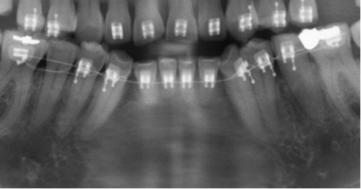

Los resultados mostraron que en el 48 % de la población se encontró algún hallazgo relacionado con la pulpa dental, con frecuencias similares entre hombres y mujeres, siendo el tratamiento endodóntico el más frecuentemente encontrado (Tabla 1, Fig. 1). El rango del número de endodoncias por radiografía fue de 1 a 18. El 86,4 % de las radiografías presentaron de 1-5 endodoncias, 11,4 % de 6-10 y el 2,2 % de 11-18. La presencia de zona radiolúcida periapical seguida por la reabsorción (Fig. 2), fueron los siguientes hallazgos más frecuentes. (Tabla 1)

Los otros hallazgos analizados (Fig. 3) se presentaron en muy baja frecuencia. Para ninguno de los casos, se encontraron diferencias estadísticamente significativas entre hombres y mujeres.

El análisis de la presencia de zona radiolúcida periapical, mostró que del total de dientes en boca, el 0,6 % de los que no tenían endodoncia tienen lesiones apicales mientras que el 11% de los que tienen endodoncia se asocian con una lesión apical (p<0,000000). Sin embargo el cálculo del OR (OR=0,047) mostró una relación negativa de riesgo entre tener una endodoncia y presentar lesión apical. De los 389 dientes en los que se observó el hallazgo compatible con radiolucidez periapical, 171 (44 %) tenían tratamiento endodóntico, de los cuales 66 % estaban subobturados, 31% bien obturados y 3% sobreobturados.

Un hallazgo importante en este estudio fue encontrar que el 52,7 % de los dientes se consideraron subobturados, asociados en un 66% con lesiones apicales vs el 44.9 % en aquellos que estaban en límites de normalidad. Esto coincidiendo con De Moor y colaboradores 11 que encuentran que del 6,8 % de dientes que están obturados, el 56,6 % fueron considerados mal obturados. Un análisis utilizando tomografía de rayo de cono, mostró que el 23,04 % de dientes están mal obturados y en ellos el riesgo de tener una lesión apical aumenta en 4,38 veces17. Un estudio de Moreno y colaboradores18 mostró que el 51% de los dientes tratados, no presentaban patologías perirradiculares y solo el 33% se consideraron correctamente obturados.